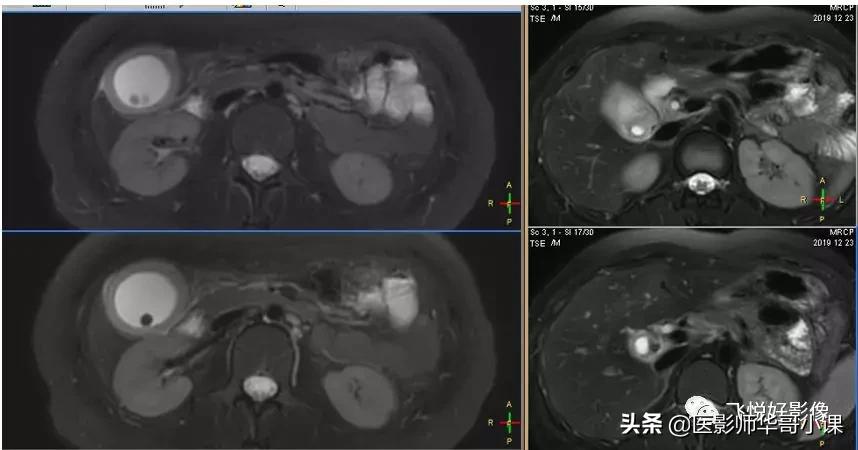

2D MRCP胆囊颈显示不清,无法重建。

3D_MRCP_BH可以进行3D重建,找到“责任病灶”。